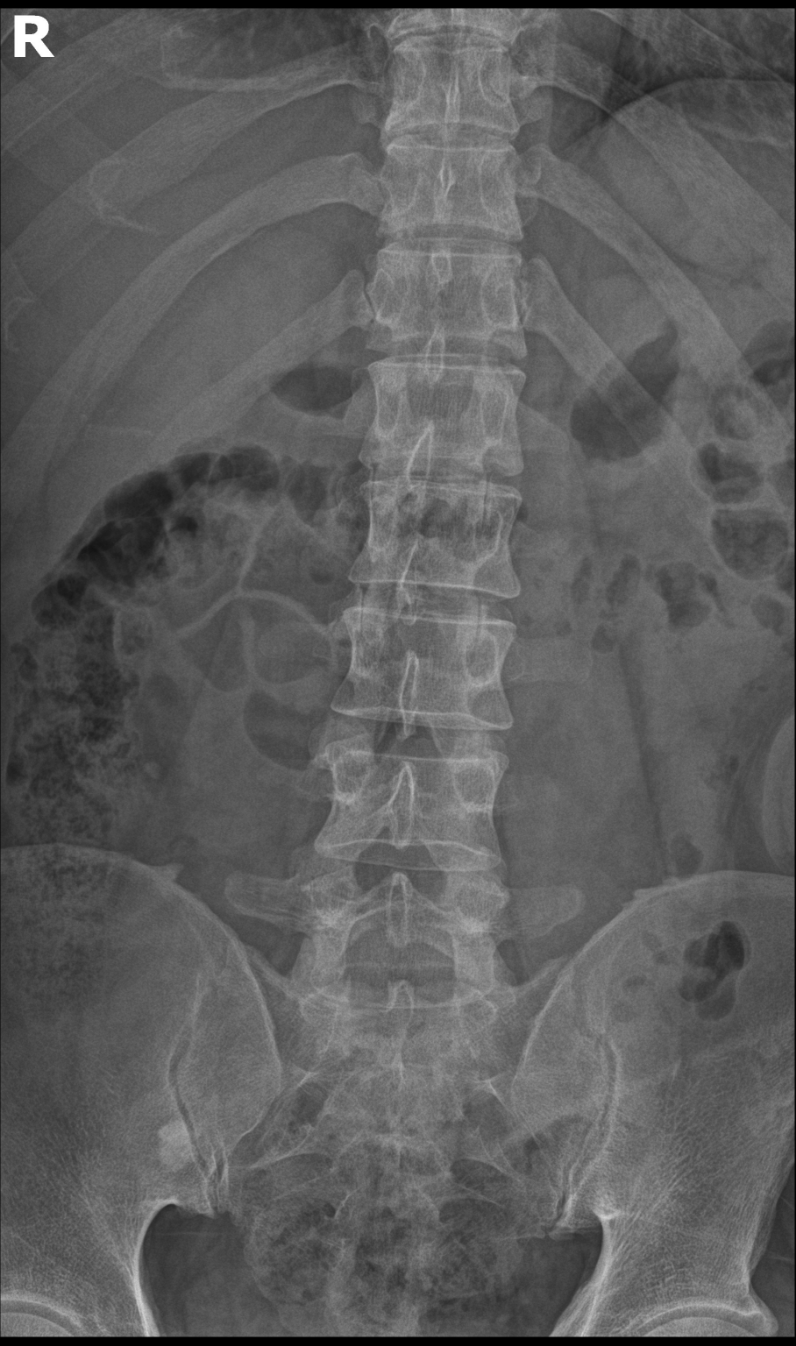

AP or PA